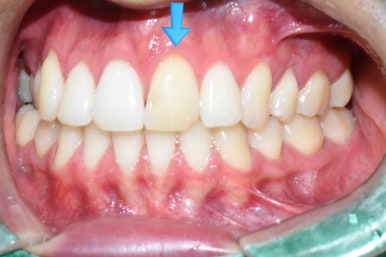

앞니 하나가 오래 전에 변색되었어요

이 외국 환자분은 오래 전에 치아 하나가 변색되기 시작했고

그래서 2년 전 쯤에 본인 나라(유럽)에서 신경치료를 시도 했으나 신경관이 너무 좁아서 신경관을 찾지 못해

중단된 상태였습니다.

위 앞니 하나가 아주 변색이 된 상태 (치료 전)

변색된 앞니

딱 눈에 보이는 가장 큰 앞니 하나가 변색이 너무 심하니